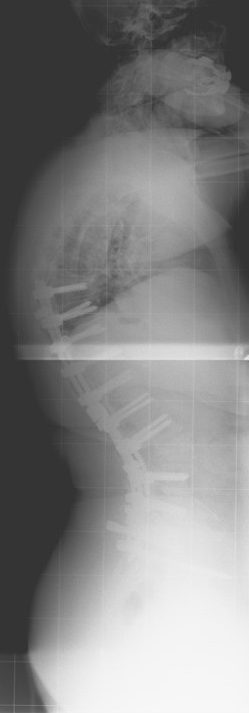

60 Yaşında Kadın Hasta

Ameliyat Öncesi